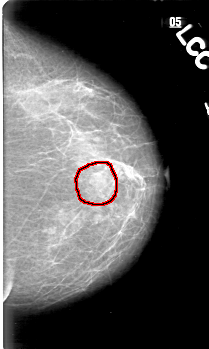

D_4033_1.LEFT_CC

LEFT_CC LINES 5221 PIXELS_PER_LINE 3121 BITS_PER_PIXEL 12 RESOLUTION 43.5 OVERLAY

FILE: D_4033_1.LEFT_CC.OVERLAY

TOTAL_ABNORMALITIES 1

ABNORMALITY 1

LESION_TYPE MASS SHAPE IRREGULAR MARGINS ILL_DEFINED

ASSESSMENT 0

SUBTLETY 5

PATHOLOGY BENIGN

TOTAL_OUTLINES 1

BOUNDARY